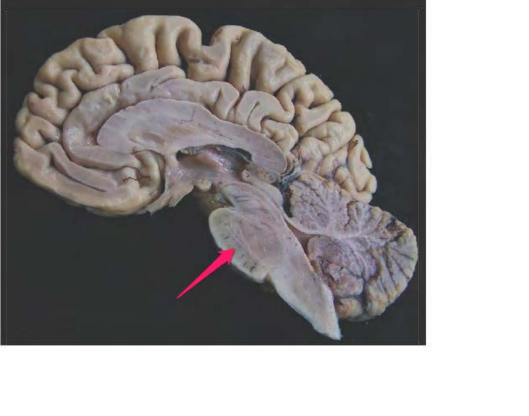

tonsilla cerebelli sin.